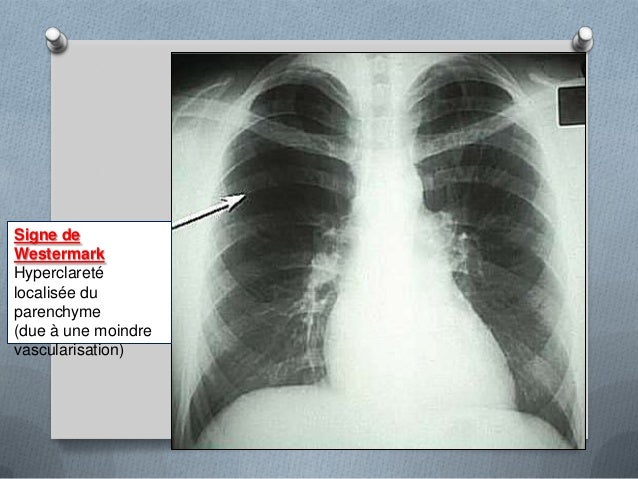

Aide au Codage CIM 10 embolie pulmonaire poumon CCAM et CIM10 en Français Site gratuit de codes CIM10 et CCAM, compatible AMELI, dédié au PMSI. Introduit un infarctus pulmonaire de la maladie La première raison est l'apparition de caillots sanguins dans les vaisseaux sanguins Lorsque le blocage de la lumière du vaisseau par un caillot de sang, une personne commence une attaque. Infarctus pulmonaire Image dœdème pulmonaire Les signaux pleuraux Comblement dun cul de sac pleural Épanchement scissural Ascension dune coupole diaphragmatique 2 Électrocardiogramme ECG normal 25 % des cas Tachycardie sinusale Déviation axiale droite , aspect S1 Q3.

1er épisode WhyDoc l'embolie pulmonaire Savezvous ce que c'est ?. Évolution de l’infarctus pulmonaire Résorption en 4 à 8 semaines « meltingsign » Image séquellaire linéaire, / rétractile 1 infarctus sub aigu à tendance rétractile 2 infarctus sub aigu atélectasie débutane et epanchement réactionnel. Embolie pulmonaire PDF Occlusion aiguë d’une artère pulmonaire ou d’une ou plusieurs branches des artères pulmonaires par un caillot fibrinocruorique migré d’une veine thrombosée, (située en général au niveau des membres inférieurs) Classe Cour de médecine PDF Module.